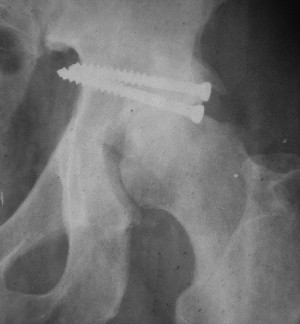

Послеоперационный снимок прямой 5/05/03

|

Больной 18 мая 2003 года в автоаварии получил перелом левой вертлужной впадины, вывих бедра. Госпитализирован в один из стационаров области.Вывих вправлен. В последствии бедро вывихивалось еще дважды. На консультацию был представлен снимок от 19.05.03г., больной переведен к нам 3.06.03г. Снимок при поступлении - перелом впадины, задне-верхний вывих бедра. 05.06.2003 г. выполнено открытое вправление вывиха левого бедра и остеосинтез стенки вертлужной впадины двумя винтами. Послеоперационный период без осложнений. Объем движений в левом тазобедренном суставе восстановился полностью. Выписан на амбулаторное лечение в удовлетворительном состоянии с рекомендациями 3 месяца ходить на костылях без нагрузки на оперированную конечность. На контрольных рентгенограммах левого тазобедренного сустава 13.10.2003 г. - признаки консолидации перелома; плотность, форма головки и состояние суставных поверхностей удовлетворительные. Разрешена дозированная осевая нагрузка, на конечность с использованием дополнительной опоры. 19.12.2003 г. больной обратился с жалобами на боли в левом тазобедренном суставе. На рентгенограммах левого тазобедренного сустава 19.12.2003 г., 20.02.04г. - асептичекий некроз головки бедра. 5.04.04г. - эндопротез. Сейчас ходит без трости, не хромает. Особенность эндопротезирования - при удалении винтов прослежена линия перелома заднего края впадины и предложено установить чашку несколько меньшего диаметра, чтобы она была покрыта несломанной частью.